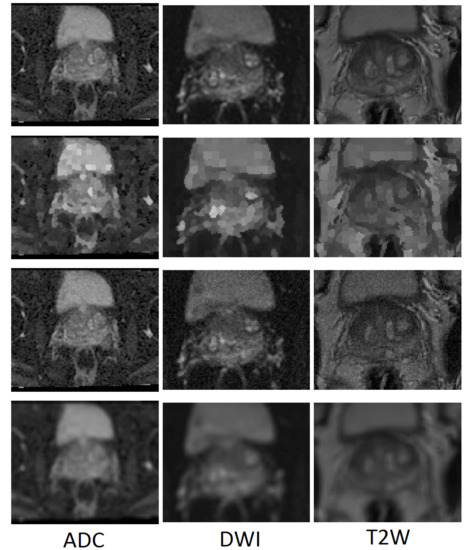

In order to examine the generalisability of the models on another representative set of MR images acquired in a clinical setting, the publicly available dataset (PROMISE12) [25] was used. This dataset contains 50 cases including T2-weighted MR images of the prostate. This dataset is multi-center and multi-vendor and has different acquisition protocols, with various prostate sizes and appearances. Details of the acquisition protocols for the different centers is explained by Litjens et al. [25]. Due to different MRI protocols (e.g., differences in slice thickness, magnet strength, with/without endorectal coil), the quality of the images was different in this cohort. Figure 2 shows some slices from different data cohorts to show appearance differences. There is a spread in prostate sizes and appearance in all images in our clinical cohort and the public dataset.

Figure 2.

Some slices from different data cohorts to show appearance differences with T2 modality. First row: PROMISE12 dataset. Second row: our clinically collected dataset.

In terms of the T2W modality, similar outcome was achieved with regards to the training samples used during learning procedure for the cGAN model. The combination of raw and GNA was the best in the cGAN model; while the combination of raw and SP obtained the best output results in the cycleGAN model. To justify this by investigating the T2W modality images, we observed that the images in this modality show anatomy, especially the peri-prostatic structures, more clearly than other modalities. Figure 6 shows that ADC and DWI images have low signal around the prostate compared to the T2W modality. Superpixelizing the T2W images groups the pixels better and makes the surrounding anatomy more visible for the cycleGAN network. In the cycleGAN model there are two different domains and there is no paired input-output relation between them. The generators are penalized by the adversarial loss with the cycle consistency loss, which forces the generators to not only do the segmentation but also synthesize the original MR image from the created mask back again. As a result, the network learns a mapping between the training images and their masks and vice versa. Therefore, for the SP approach, learning is more optimised. When we compare the results of the raw plus SP images on the three modalities in the cycleGAN model, it is also consistent with this result that training using the T2W modality images obtained the best results (with DSC values of 0.748) while the DSC outcomes for DWI and ADC modalities were 0.702 and 0.710, respectively. For the DWI modality, the best results for the cGAN and cycleGAN models were achieved by using the raw plus MM images as the training set. The MM approach removes the unnecessary details from an image helping the network to focus on prostate tissue as the target part of the image during the training process. It shows consistent results with regards to the three evaluation metrics. The ROC curves and AUC values for these networks, applied to three modalities (ADC, DWI and T2W), are shown in Figure 7.

Figure 6.

Some examples of T2W, ADC and DWI MR images from our dataset, which demonstrates that DWI and ADC modalities have lower signal around the prostate compared to the T2W modality. Scaled images are shown in Figure A2 for better visualisation.

Figure A2.

Some examples of T2W, ADC and DWI MR images from our dataset, which demonstrates that DWI and ADC modalities have lower signal around the prostate compared to the T2W modality.